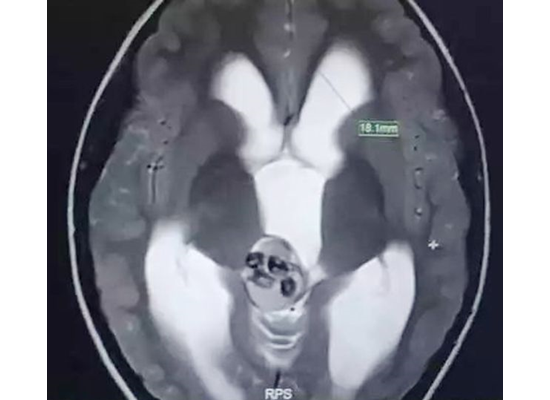

في حالة طبية غريبة تُعد الأولى من نوعها، عثر أطباء من مستشفى الأطفال في جامعة تشجيانغ الطبية، شرق الصين، على 9 أسنان تنمو داخل دماغ طفل يبلغ من العمر 5 أعوام.

وأوضح زهيبنج أن حالة الطفل ناجمة عن ورم نادر لم يكتشف منذ ولادته، حيث شكل هياكل عظمية من الأسنان داخل دماغه.